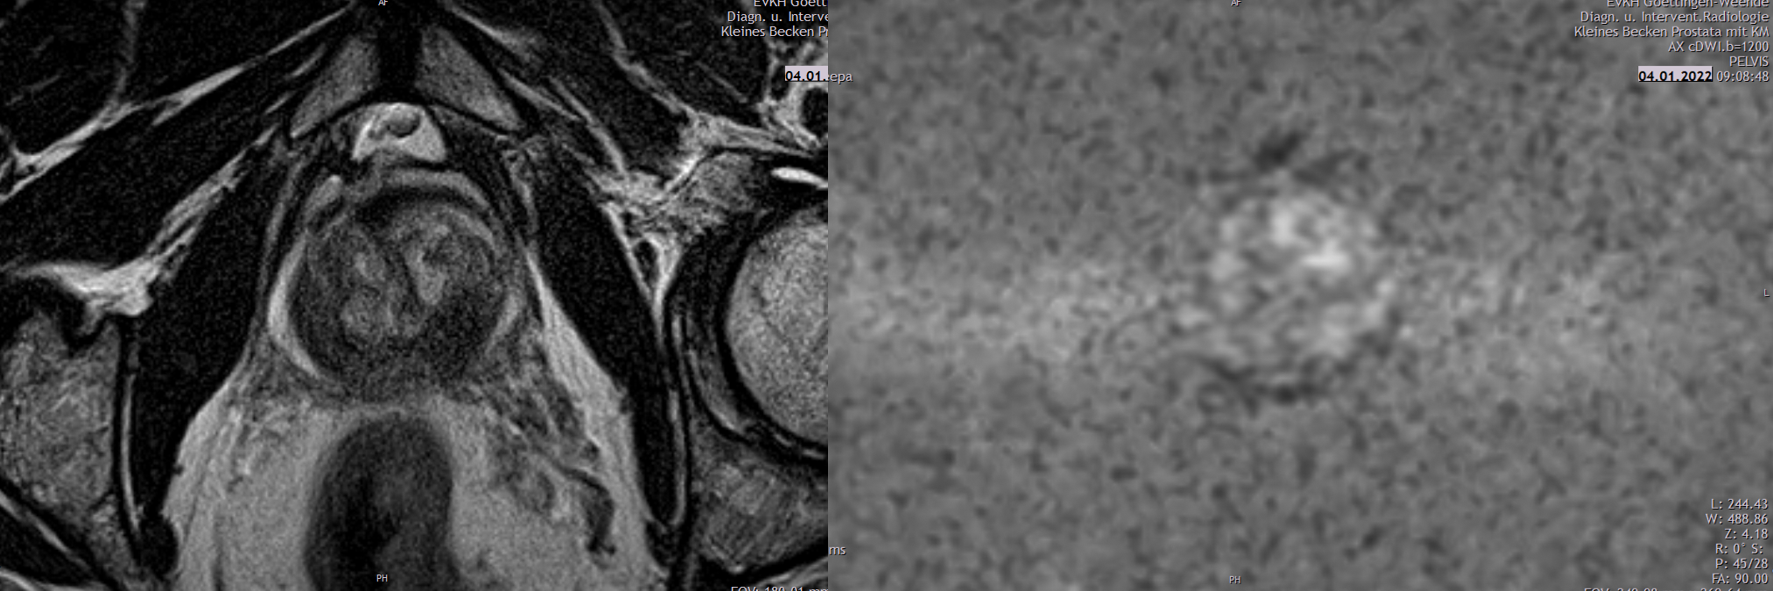

Urogenitale Radiologie, multiparametrische Prostatabildgebung

Es handelt sich um ein medizinisches MRT-Bild des Beckens, das die Prostata darstellt.

Es zeigt medizinische Bildgebung des Beckens mit farblich hervorgehobenem Bereich, möglicherweise zur Analyse von Gewebe.

Aufgaben der urogenitalen Radiologie sind – neben nichtonkologischen Krankheitsbildern wie Nierensteinen – die Darstellung und Charakterisierung von urologischen Neoplasien, die Suche nach ihren Metastasen im Rahmen des Tumorstagings, die Therapiekontrolle und die radiologische Tumornachsorge. Häufig untersuchte Tumore sind das Nierenzell-, Blasen- und Prostatakarzinom. In unserem Institut setzen wir mit der 80-Zeilen Multidetektor-CT und der 3 Tesla MRT hochmoderne Untersuchungsverfahren ein. Diese werden kontinuierlich weiterentwickelt und dem Stand der Wissenschaft angepasst. So hat sich in den letzten Jahren beispielsweise das multiparametrische MRT (mpMRT) der Prostata als optimales Verfahren bewährt, um Prostatakarzinome zu entdecken und darzustellen. Mit dieser strahlungsfreien Methode können wir Tumorherde identifizieren und klassifizieren. In der Abteilung für Urologie können so gezielt Gewebeproben entnommen werden, die auch kleinste Tumorareale erfassen. Wir nutzen bei urologischen Tumoren in besonderen klinischen Situationen nicht nur die bildgebende Diagnostik, sondern auch therapeutische interventionell-radiologische Verfahren, wie die Embolotherapie bei Neoplasien der Nieren.

MRI-Bild der Prostata, Umrisse und Parameter eines Tumors, Diagramme zur Fortschrittanalyse, Olea Medical-Logo.